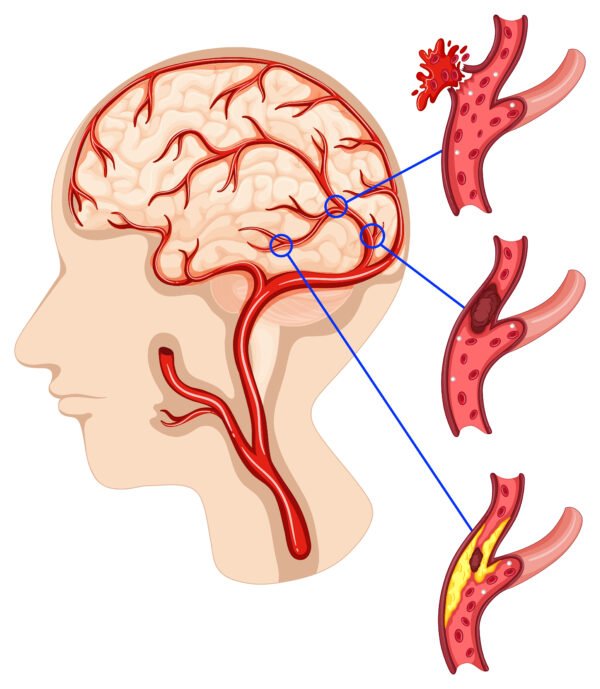

- Stroke